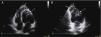

A 36-year-old woman was referred for medical evaluation prior to non-cardiac surgery. She was healthy and only complained of sporadic palpitations. The 12-lead electrocardiogram showed sinus rhythm and left bundle branch block. Transthoracic echocardiography revealed a normally functioning, slightly dilated left ventricle (LV), with the interventricular septum bulging toward the right ventricle (RV), which was elongated and wrapped around the LV (Figure 1; Supplementary material Videos S1 and S2). The papillary muscles were structurally abnormal and presented an apical origin, findings better visualized in contrast images (Figure 2; Videos S3–S5). Cardiac magnetic resonance confirmed the presence of a truncated LV, a complex network of papillary muscles of apical origin, and a banana-shaped, normally functioning RV (Figures 3 and 4; Videos S6–S8). There was no evidence of fatty infiltration or late enhancement with gadolinium.